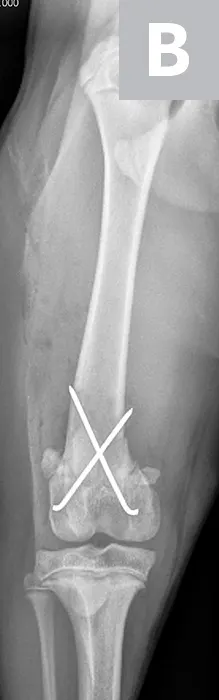

Hydromorphone (0.05 mg/kg IV) was administered for analgesia, and lateral and ventrodorsal thoracic radiographs were obtained to evaluate for thoracic trauma. Radiographic findings were within normal limits; however, lateral and craniocaudal radiographs of the right pelvic limb (Figure 1) revealed a Salter-Harris type II fracture of the distal femur with caudal and medial displacement.

Figure 1

Lateral (A) and craniocaudal (B) radiographs of this patient’s femur. A Salter-Harris type II fracture with caudal and medial displacement is present in the distal femur. The metaphyseal component (A; arrow) and the epiphyseal component (arrowhead) can be noted.